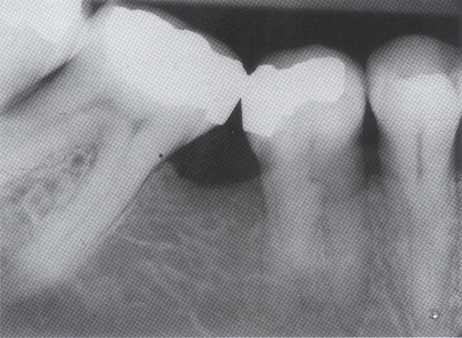

Treatment of maxillary molars is never routine (Figure 2-22). In a recent study of maxillary first and second molars an MB2 canal was found in 96% of the mesiobuccal roots of maxillary first molars and 94% of the maxillary second molars. Approximately 54% were located in the traditional access opening, 31% were found with the use of a bur, and 10% were found with the aid of a microscope. The MBZ canal orifice was found on average 1.82 mm lingual to the main MB canal orifice.9 In another study of the maxillary first molar using microscopy, the MB Z canal was located in

93% of first molars and 60% of second molars4 (Figures 2-23 and 2-24). The difficulty in access, high percentage of fourth and even fifth canals, and root curvatures put even the "routine" maxillary molar in a high-risk category.3 Complicating factors such as limited opening, crowns, changes in tooth angulation, tooth position, and calcification make predictable treatment of these teeth challenging for even the most experienced clinician trained in microscopy, ultrasonics, and rotary instrumentation.

termine the percentage of cases with at least four canals. If the percentage is less than 45% for first molars or less than 35% for second molars, these cases should be carefully screened for referral because the MBZ canal is being missed and untreated about half of the time.

Guidelines for canal location in the maxillary first molar (Figure 2-25) differ from that in the maxillary second molar. In the maxillary first molar the MB canal is located under the mesial buccal cusp (see Figure 2-25, D). The MBZ canal is located mesial to a line from the

MB canal toward the palatal canal (see Figures 2-25, E, and 2-26). The DB canal is located distal to the MB canal in the buccal groove area, slightly lingual to the MB canal (see Figure 2-25, G). The palatal canal is generally the largest canal and is located under the mesiolingual (ML) cusp (see Figure 2-25, F). These general locations remain the same as the pulp calcifies with age (Figure 2-27). Although these general principles apply to the maxillary second molar, the chamber may be narrower, resembling a straight line (see Fig. 2-55).